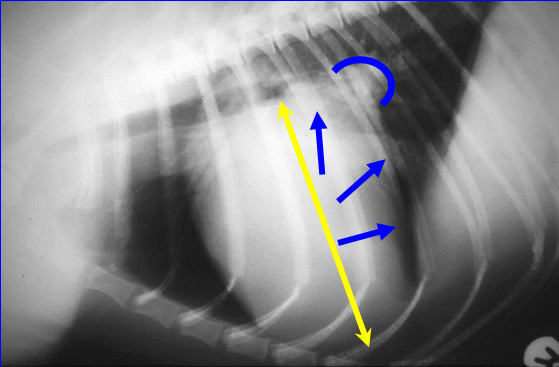

Left-sided heart enlargement in dogs

If LHS enlarged, LV will spread caudally and also dorsally to some extent. So caudal aspect will be displaced and straight than usual

Tall heart